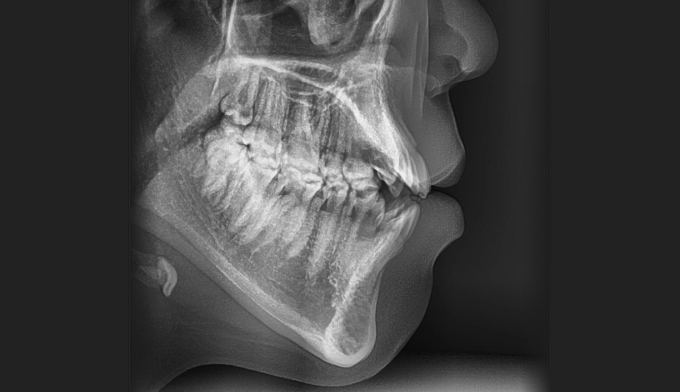

개방교합은 좋지않은 발음을 만들기도 하지만 심미적으로도 좋아보이지 않아서 교정치료를 받으러 많이 오십니다. 치아는 가지런하므로 교정치료가 어렵지 않아 보이지만 개방교합의 치료는 교정용 미니스크류의 식립도 필요하며, 재발도 잘되는 어려운 교정입니다. 교정치료 이후에 재발되지 않게 주기적인 관리 및 연습도 필요합니다.

어금니의 미니스크류의 식립을 통하여 개방교합을 치료하였습니다. 총 치료기간은 13개월입니다.